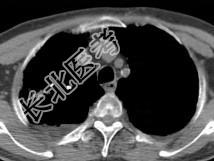

- 单项选择题男,76岁, 气喘数年,胸痛一月余, 结合影像图像,选择最可能的诊断 ( )

A、右上肺结核球

B、肺间质纤维化

C、右上肺瘢痕癌

D、右上肺错构瘤

E、右上肺肉瘤